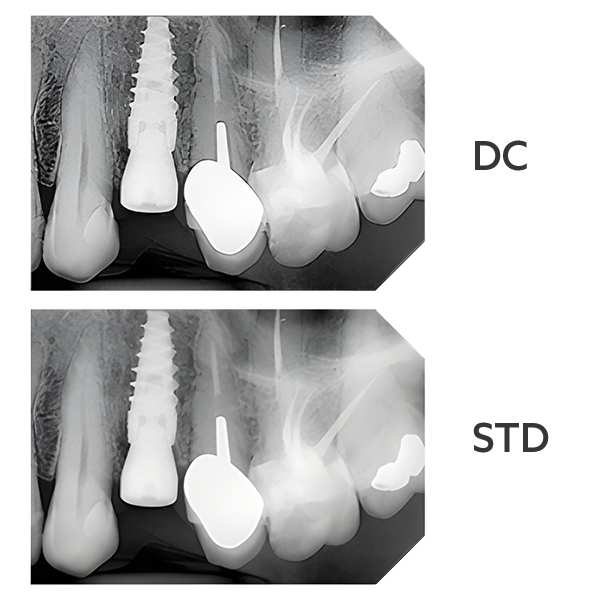

Traditional intraoral sensors rely on scintillators to convert X-rays into visible light before being captured by the sensor. While effective, this multi-step process can introduce noise and diminish image quality.

Direct conversion technology in the NewTom DCiS works differently:

For dentists, this isn’t just about technology; it’s about empowering your clinical judgment. With the NewTom DCiS you can diagnose with confidence on the first scan, minimise repeat exposures, and focus on the best outcomes for your patients.

Clear, high-contrast images aren’t just a convenience - they’re essential. Every detail captured by the NewTom DCiS can make the difference between a timely intervention and a missed complication.